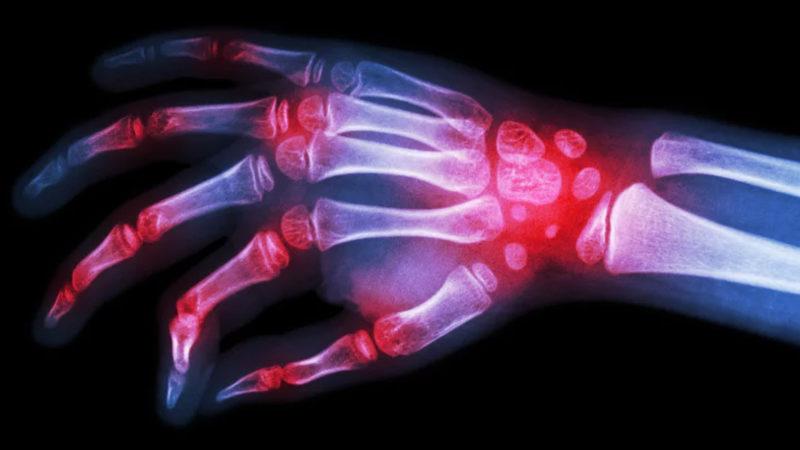

Bilim insanları, bugüne kadar nedeni tam olarak anlaşılamayan ve günlük yaşamı doğrudan etkileyen hastalıklarından bir tanesi olan Romatoid artrit hastalığıyla ilgili yeni bir ilaç üzerinde çalışıyorlar. İltihaplı romatizma olarak da bilinen bu hastalık için üretilen bu ilaç, son deneylerden de başarıyla geçti ve ilerleyen dönemlerde hastalar tarafından kullanılabilmesi için önümüzdeki bir yıl içerisinde piyasaya sürülecek.

Filgotinib olarak isimlendirilen bu ilaç, JAK1 enzimini hedef alıyor ve bu sayede Romatoid artrit hastalığının iyileştirilmesini sağlıyor. Bilim insanları yaptıkları ilk testlerde, 12 hafta boyunca bu hastalıktan muzdarip olan hastalara bu ilaçlar verildi ve sonuçlar gözlendi. Bu testlerde başarı oranının yüzde 40'tan fazla olduğu belirlendi. Süreç, 24 haftaya çıktığı zamansa hastaların yüzde 50'lik kısmında ciddi bir iyileşme görüldü. Bu ilacı yüksek dozda test eden hastaların yüzde 30'unda ise, 24 haftalık kullanımdan sonra herhangi bir sorun kalmadığı tespit edildi.